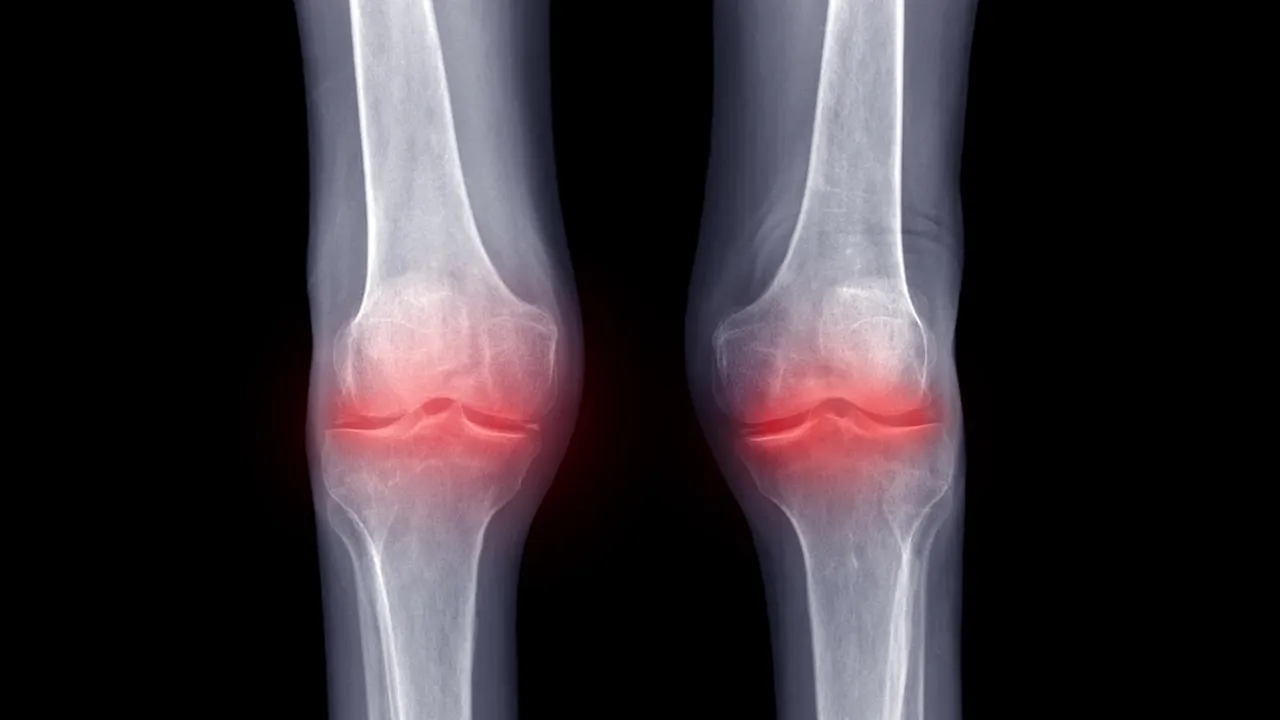

Artritin eklemlerde ağrı, şişlik, kızarıklık ve fonksiyon kaybına yol açtığını ifade eden Doç. Dr. Şevgin, “Artrit grubu hastalıkları kişinin yaşam kalitesini etkilemekte ve günlük yaşam aktivitelerinin sınırlandırmaktadır. En sık görülen türleri osteoartrit, romatoid artrit ve ankilozan spondilit olarak karşımıza çıkmaktadır.” dedi.